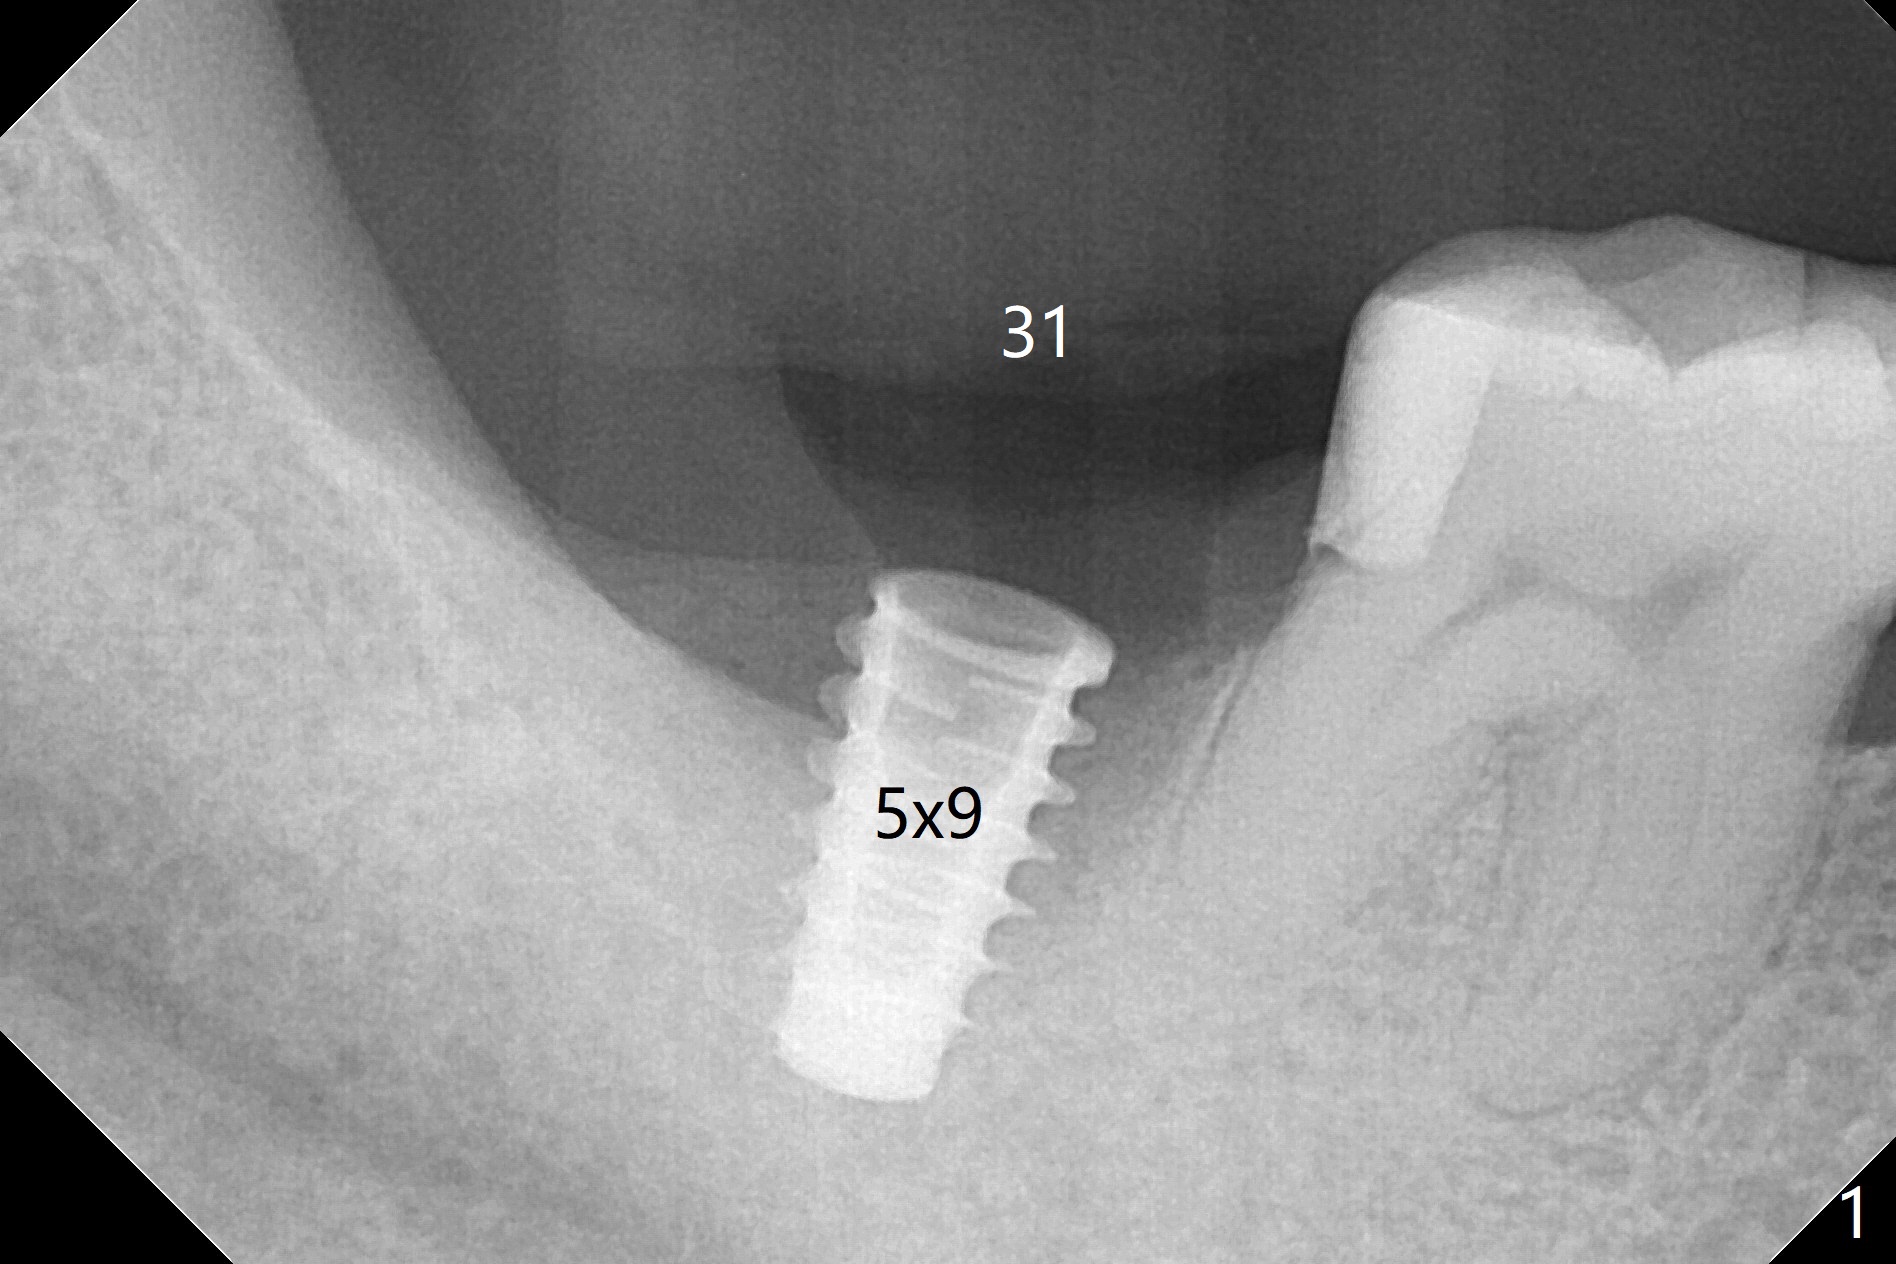

As expected, the buccodistal plate is low after extraction at #31. Osteotomy is initiated mesiolingually with 2 mm initial drill, 2.8 and 3.6 mm round drill with 4 mm stopper. The patient feels pain before the last drill reaches the depth. A 5x9 mm IBS dummy implant is placed with stability (Fig.1). When the definitive implant (5x9 mm) is placed, stability is lost. A 5.5x9 mm dummy implant achieves stability, while the definitive one loses stability. Increase in depth with 4.3 mm Magic Drill meets pain. Hemorrhage is another factor. When hemostasis is temporarily controlled, bone core is found. Nor removal of bone core with Final Drill or addition of allograft (Vera, .2-1.0 mm) in the osteotomy helps obtaining stability. Finally socket preservation is performed (Fig.2).